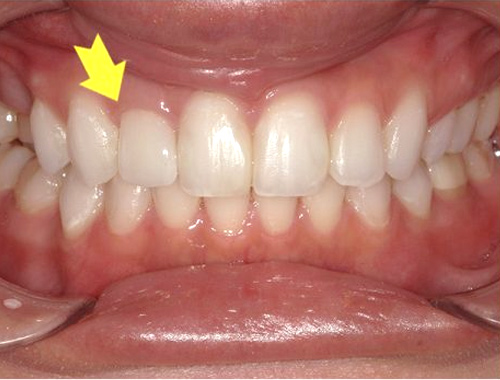

保険診療で使用されていた金属の詰め物(いわゆる銀歯)を、白くて自然な見た目のセラミック(ジルコニア)に変更した症例です。金属の詰め物は強度に優れている一方、笑ったときや口を開けたときに目立ちやすく、長い年月が経つと金属成分が溶け出して歯ぐきが黒ずんで見えることがあります。

それに対し、セラミックの詰め物は見た目がとても自然で、天然歯とほとんど見分けがつかない仕上がりが可能です。金属を一切使用しないため、金属アレルギーの心配がなく、身体にも優しい素材です。

今回使用したジルコニアは、セラミックの中でも特に強度に優れており、歯を薄く削って作製できるという利点があります。一方で、オールセラミックに比べると透明感はやや出にくい素材です。患者さまから「なるべく歯を削らず、強度も確保したい」とのご要望があったため、このジルコニア素材を選択しました。精密に作製されるため適合性にも優れており、しっかりとフィットして虫歯の再発を防ぐ効果も期待できます。

写真では、治療前後の違いをご覧いただけます。黄色い矢印の部分が、実際にセラミックに置き換えた箇所です。治療後は口元の印象が明るくなり、患者さまにも大変ご満足いただけました。

治療期間通院3回(むし歯治療、型取り、セット)、約2週間程度

費用目安税込77,000円×2